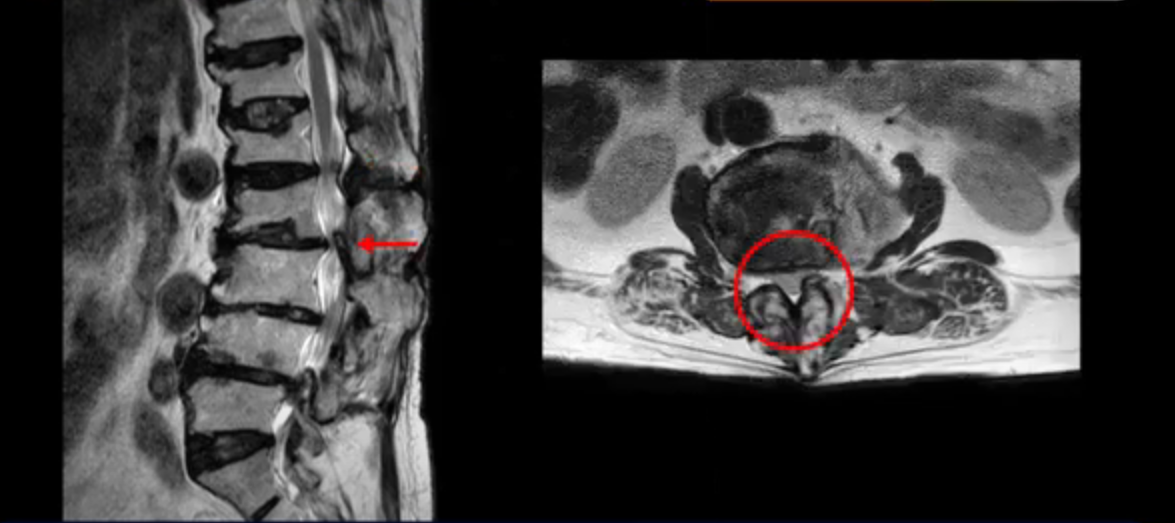

보시다시피 4번 5번 마디에는 심한 중심성 협착이 있고

3번 4번에도 중심성 협착이 있습니다.

또 신경 가지가 빠져나가는 추간공도 좁아져 있습니다. 이런 이유로 환자분의 다리가 저리고 아픈 겁니다.

또한 척추뼈 여러 개가 압박 골절과 변형으로 찌그러져 있고

골다공증도 심하시고 보시다시피 근육량이 너무 적습니다. 근육이 정상적인 분들과 비교해보면 근육이 얼마나 적은지 알 수 있습니다.